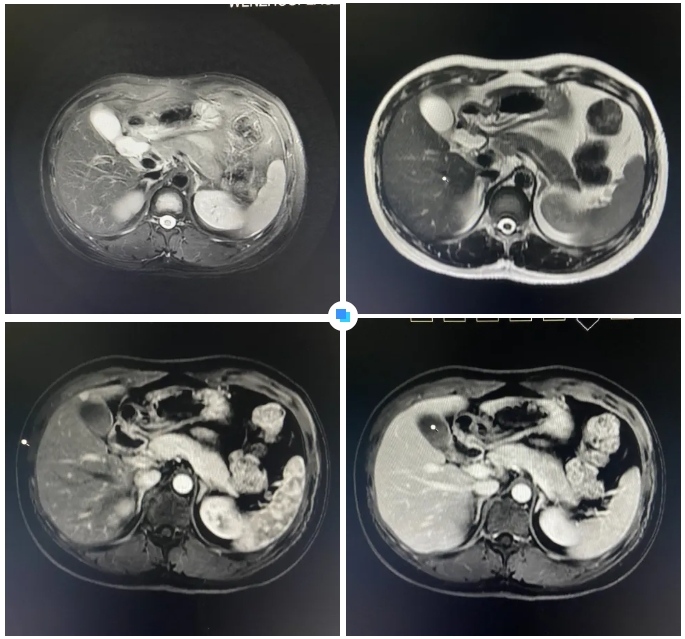

在被問到如何發(fā)現(xiàn)隱藏如此深的病灶時(shí),和平國際醫(yī)院影像中心執(zhí)行主任侯文杰講到,該病灶在平掃T1、T2項(xiàng)都非常不清楚,只有彌散加權(quán)的情況下,病灶區(qū)域顯示出輕微的高信號,這一細(xì)微線索引起了他的高度關(guān)注。

隨后的增強(qiáng)核磁掃描發(fā)現(xiàn),在動脈期病灶顯著強(qiáng)化,而在門脈期明顯減退,這一特征與微小肝癌的表現(xiàn)高度吻合。